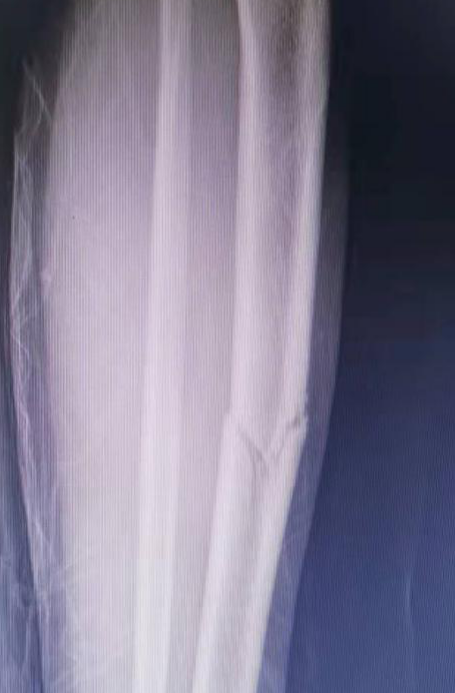

*术前X线,可见患儿股骨、双侧胫骨均出现骨折,且骨折伴有移位